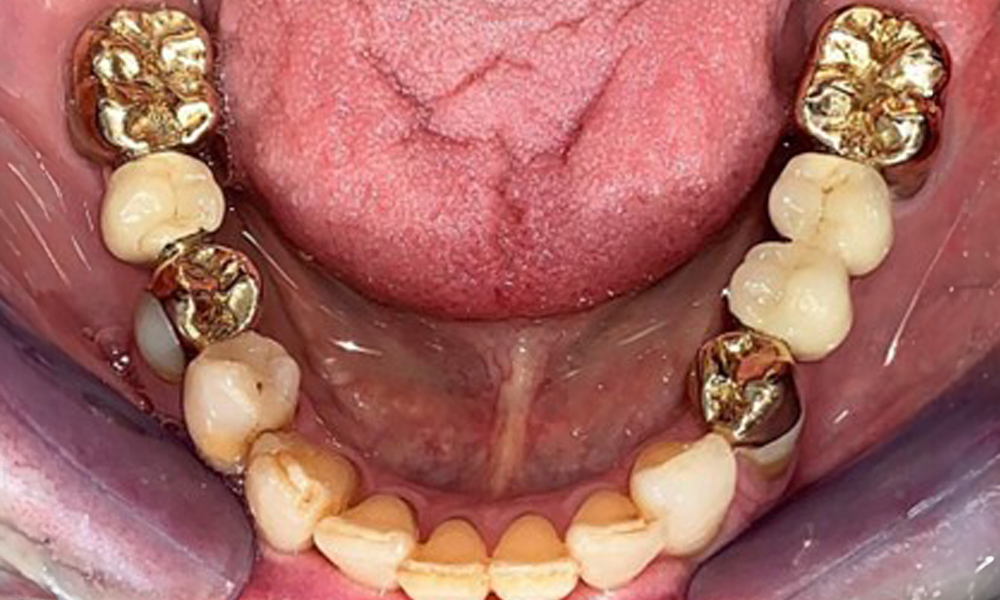

Die Patientin wurde vor über 25 Jahren mit einer kombinierten herausnehmbare Implantat-Teleskopprothese im Oberkiefer versorgt (Abb. 1, Abb. 2, Abb. 3) und ist sehr glücklich über ihren Zahnersatz. Im Unterkiefer hat die Patientin einen suffizienten festsitzenden Zahnersatz. (Abb. 4)

Der dentale Befund stellt sich wie folgt dar: Kombinierte herausnehmbare Implantat- und zahngetragene Teleskoparbeit auf Implantaten 15, 13, 21, 23, 24, 25 und Zahn 11 (Abb. 1, Abb. 2, Abb. 3). Im Unterkiefer ist die Patientin mit einem festsitzenden Zahnersatz versorgt. 37–34 sowie 45–47 haben suffiziente Brücken (Abb. 4). Kronenränder sind intakt, aktive kariöse Läsionen sind nicht vorhanden. An Zahn 43 zeigt sich eine Compositefüllung mit Randspalt. Im Unterkiefer liegen Rezessionen mit freiliegender Wurzeloberfläche zwischen 1 – 3 mm vor. Dies trifft auch für 11 zu.